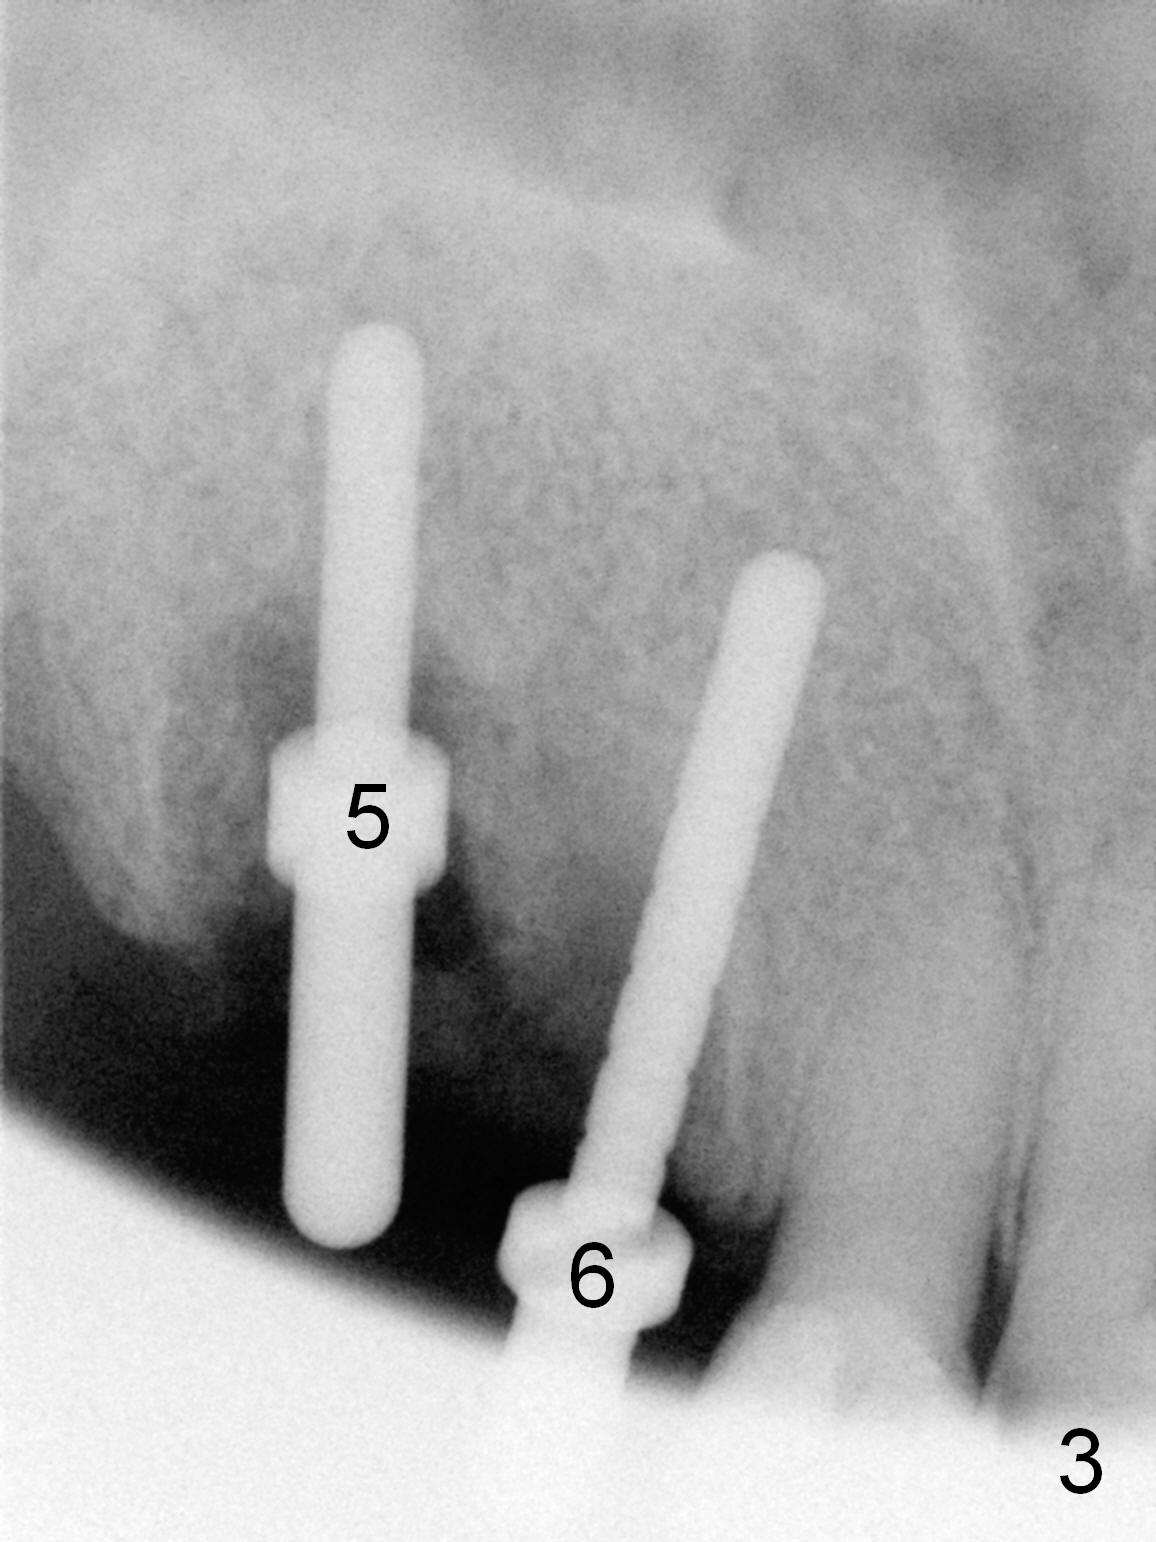

Several of CK's upper teeth (apparently in cross bite) are to be restored with implants (Fig.1). The first two are #5 and 6; note the oval roots (Fig.2). After extraction, and curettage, osteotomy starts in the palatal aspect of each socket. The 1st intraop PA shows that the trajectory at #6 is incorrect (Fig.3). After adjustment, osteotomies look parallel (Fig.4: D: 3.5x20 mm drill; T: 4.5x20 mm tap). This suggests how important it is to use parallel pins to check initial osteotomies for neighboring implants (Fig.3). The trajectory of the implants remains acceptable (Fig.5: 4.5x20 mm with insertion torque »60 Ncm); so is the position of the implants (as palatal as possible; Fig.6 (*: bone graft)). Immediate provisionals are fabricated in cross bite.